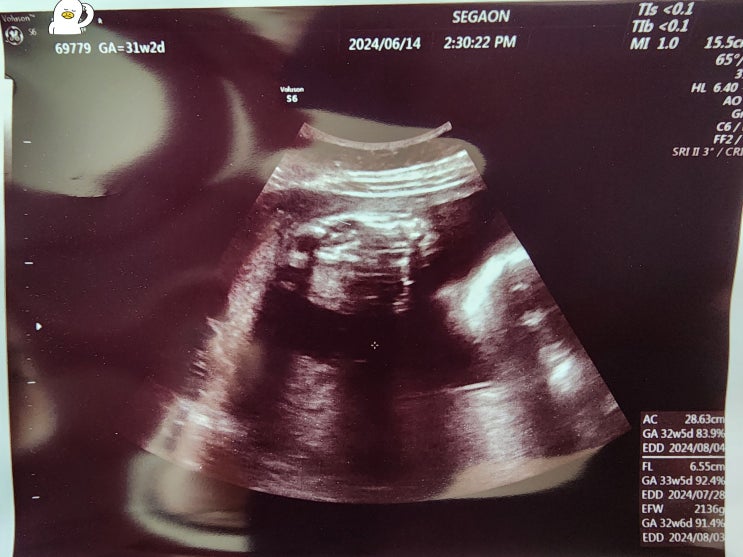

이제 임신 후반부에 접어들었다. 병원 갈 때마다 아기 크기가 크다는 이야기를 계속 듣기도 했고, 배가 점...